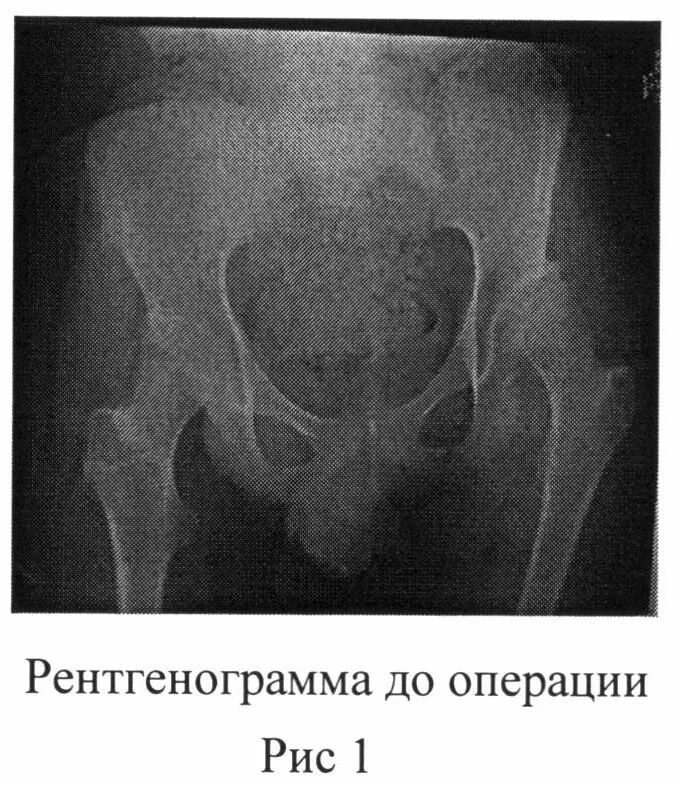

Операция при дисплазии